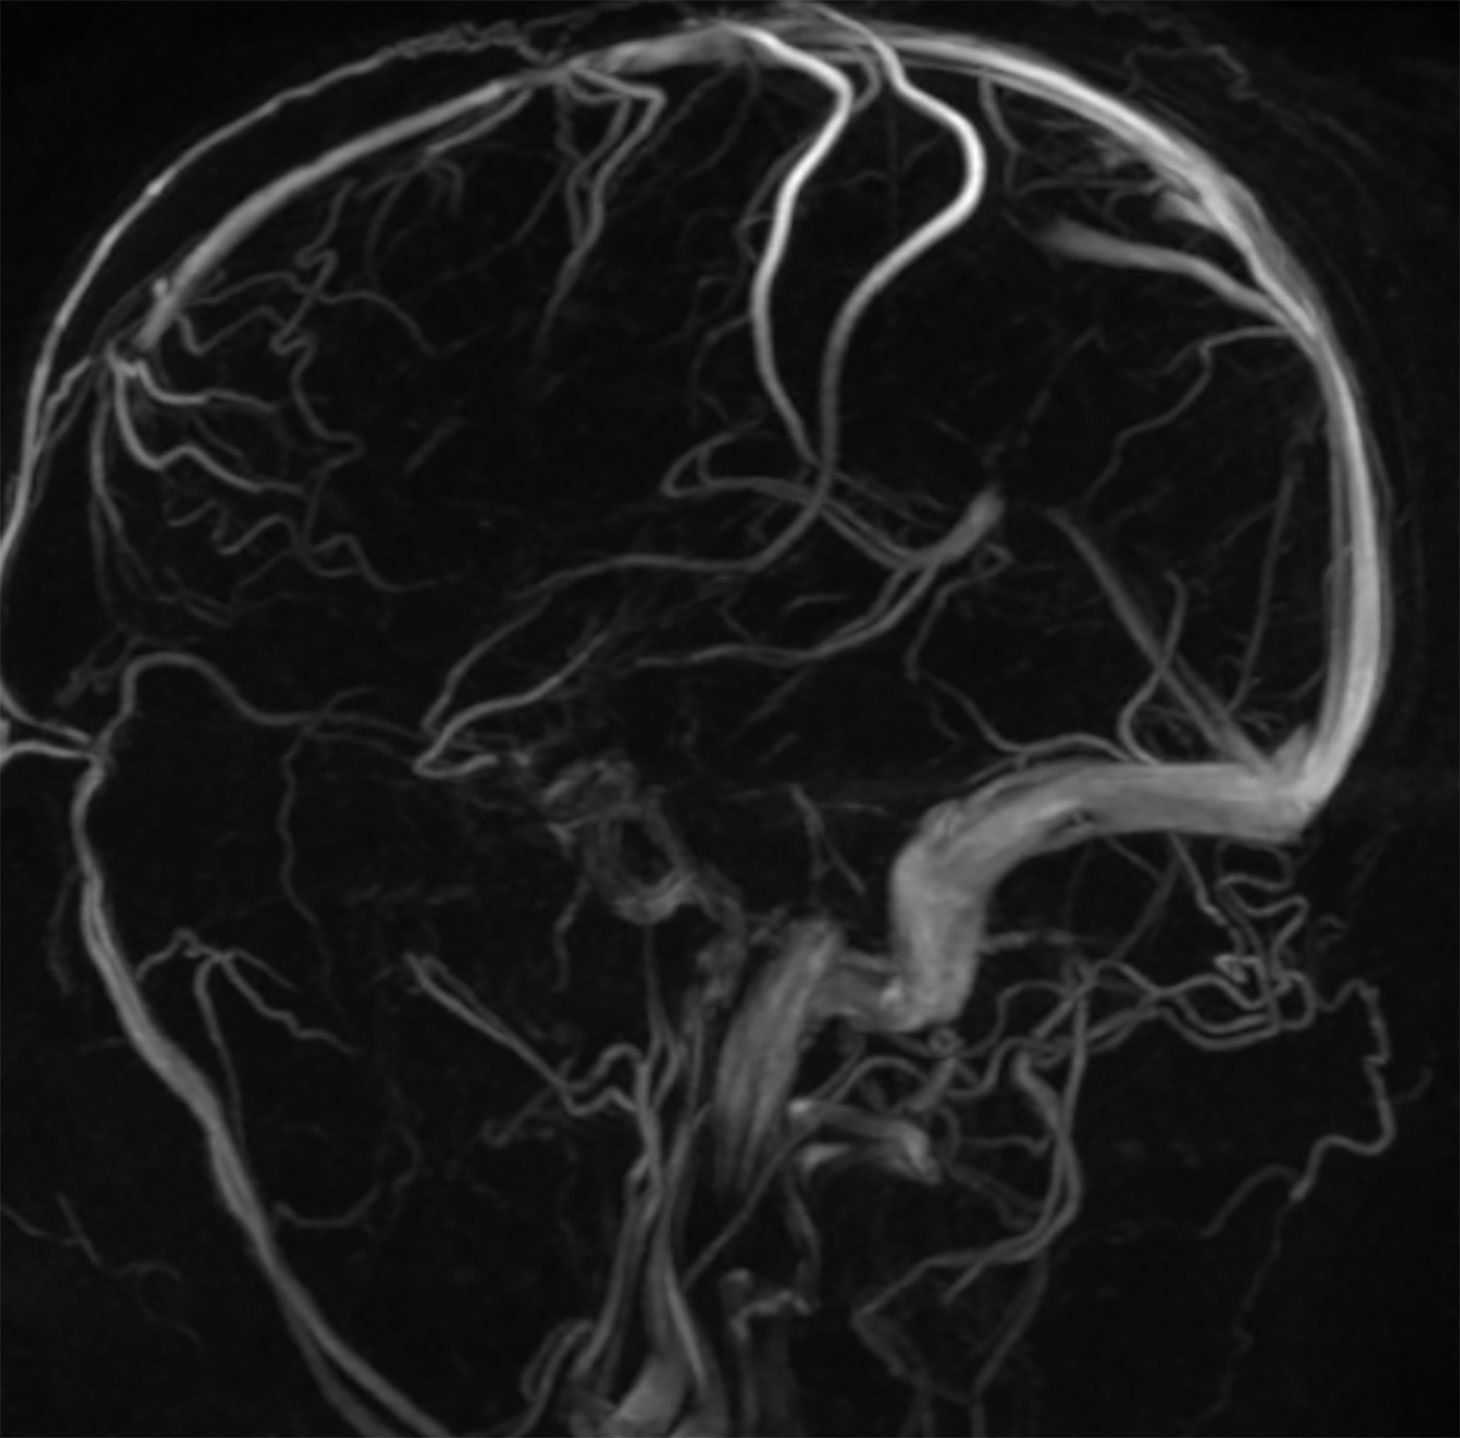

Die MRA der Gehirnarterien bietet wertvolle Informationen über die Blutzirkulation im Gehirn. Sie kann verwendet werden, um die intrakraniellen (innerhalb des Schädels liegenden) Arterien und Venen zu visualisieren, darunter die großen Hirnarterien wie die Halsschlagadern (Carotisarterien) und die Wirbelarterien (Vertebralarterien). Diese Methode ist besonders nützlich bei der Identifizierung von Durchblutungsstörungen, Gefäßverengungen (Stenosen), Aneurysmen, arteriovenösen Malformationen (AVM) und anderen vaskulären Anomalien im Gehirn.